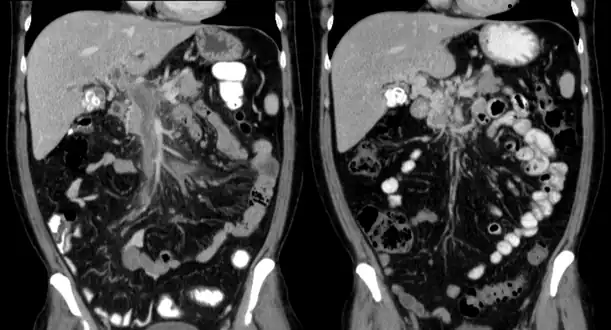

Portal vein thrombosis on computed tomography (left) and cavernous transformation of the portal vein after 1 year

The diagnosis of portal vein thrombosis is usually made with imaging confirming a clot in the portal vein; ultrasound is the least invasive method and the addition of Doppler technique shows a filling defect in blood flow. PVT may be classified as either occlusive or nonocclusive based on evidence of blood flow around the clot.[5] An alternative characterization based on site can be made: Type 1 is limited to the main portal vein, Type 2 involves only a portal vein branch (2a, or 2b if both branches are affected), and Type 3 if clot is found throughout both areas.[8] Determination of condition severity may be derived via computed tomography (CT) with contrast, magnetic resonance imaging (MRI), or MR angiography (MRA). Those with chronic PVT may undergo upper endoscopy (esophagogastroduodenoscopy, EGD) to evaluate the presence of concurrent dilated veins (varices) in the stomach or esophagus.[3] Other than perhaps slightly elevated transaminases, laboratory tests to evaluate liver function are typically normal.[1] D-dimer levels in the blood may be elevated as a result of fibrin breakdown.